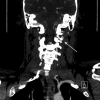

Figure 2

Figure 2. CT angiography (CTA) coronal view, shows severe narrowing of the left vertebral artery at C2 level with possible dissection (arrow).